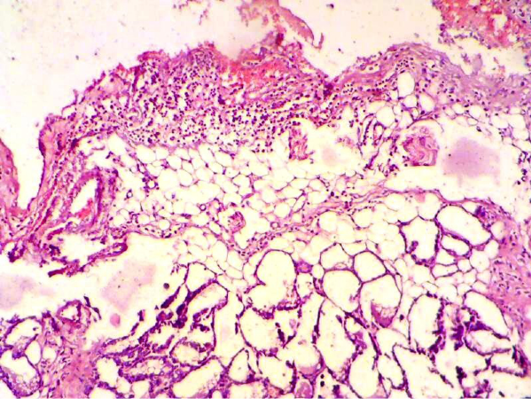

Mammary gland section shows inflammatory reaction around mammary alveoli with destruction of adipose tissue. (H&E 200 X)